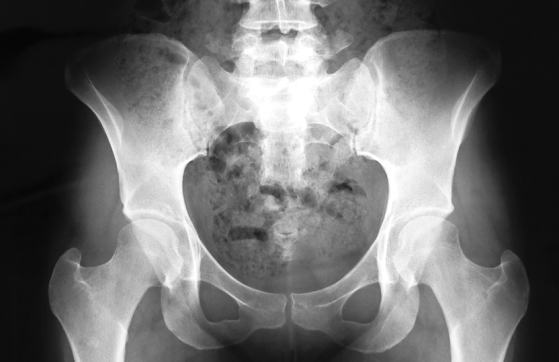

Look at the picture of the pelvis.

Can you see the proper "gap" between the bones?

This proper gap is the foundation for creating "pelvic play." This "pelvic play" isn't good for body shaping if the gap is too large or too small. In reality, there are more women with a gap that's too small and a rigid, stiff pelvis than women with a gap that's too large.